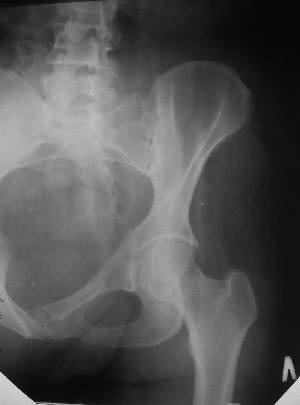

Уважаемые коллеги! Хотел-бы обсудить интерессный, на мой взгляд, случай. На консультацию пришла женщина 45 лет с отводящей контрактурой правого бедра.

Из анамнеза: в ноябре 2002г. оступилась,упала на трап самолета (на верхней площадке, сразу при выходе из салона) на правый тазобедренный сустав, а затем - вниз на землю на ноги и ягодицы. Потеряла сознание от боли. Доставлена в больницу по месту жительства, лечилась консервативно с диагнозом кокцигодиния. На рентгенограмме от 27.11.02г. вывиха копчика не определяется (снимок идентичен представленной R-грамме от28.11.03г., кроме этого есть нормальная R-грамма копчика в боковой проекции).Через три недели стала ходить, но привести правую ногу в тазобедренном суставе не могла. Сейчас ходит отведя кнаружи правое бедро и голень, как ножку циркуля (фото 1). Неврологических нарушений нет. По просьбе врача может на 30-40 секунд поставить ноги вместе (фото 2). При этом испытывает сильную тянущую боль и ощущение "вывернутости" в правом тазобедренном суставе. Эти ощущения заставляют вновь отвести бедро. В положении лежа разогнуть бедро полностью не может из-за болей в ягодичной мышце (фото 3). Сгибание также ограничено из-за болей (фото 4). Отведение в положении лежа возможно в том же объеме, что и стоя (фото 5). Заподозрен старый разрыв правого крестцово-подвздошного сочленения. Выполнено R-исследование и КТ(в приложении). По-поводу деформации лонного сочленения выяснен гинекологический анамнез. Роды одни, нормальные в 22 года. Из роддома выписана на 8 сутки, нарушения походки не было, R-графия таза не проводилась. Вопросы на обсуждение: 1. Диагноз либо алгоритм дальнейшего обследования. 2. Лечебная тактика (в первую очередь возможность и целесообразность оперативного лечения).